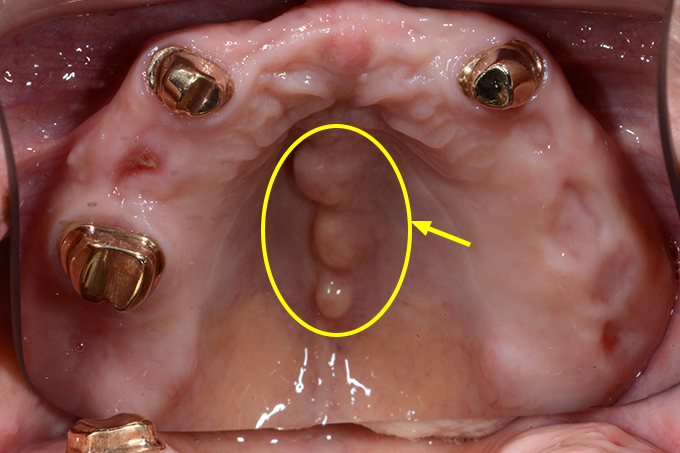

骨隆起って何?

下の写真の矢印部は、歯ぐきが膨らんで、触れると硬く骨ばっています。

ほとんどの方が気づかれてないです。中には、「えっ!?みんなあるんじゃないんですか?」

「歯ぐきが腫れてる感じがします」とおっしゃる方もおられます。

これは遺伝やかみ合わせ、強い咬合力などにより、骨が部分的に増殖したもので、上アゴの中央や下アゴの内側(ベロ側)にできることが多いです。病的なものではありません。

ただ、入れ歯を作るのに障害になることがあります。(お悩みの方はこちら)

これがある方は、歯ぎしり、食いしばり、かみしめを疑ってください。